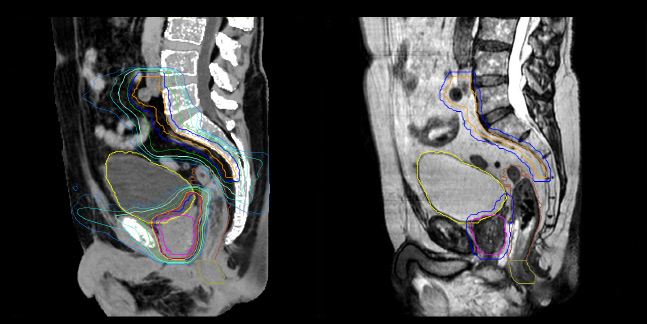

Prostate MR-only radiotherapy planning with use of rectal spacer

Hôpital de La Tour uses an implanted rectal spacer (SpaceOAR®, Boston Scientific) for patients receiving prostate radiotherapy to provide space between the rectum and prostate. 3D T2W TSE MRI provides excellent rectal spacer visualization and is used for OAR and target contouring. The dose plan is calculated on the MRCAT dataset.

MR-based contouring and planning

MRCAT is primary image dataset for dose calculation (left).

3D T2W TSE MRI with 36 cm Field-of-View is used for delineation of prostate and organs at risk (right).